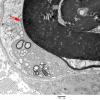

PERIPHERAL NEUROPATHY

7B CIDP (4)